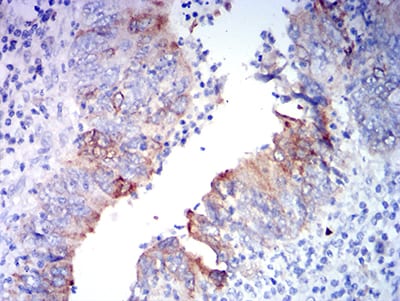

Immunohistochemistry analysis of paraffin-embedded human rectum cancer tissues using AMPA Receptor 2 antibody.